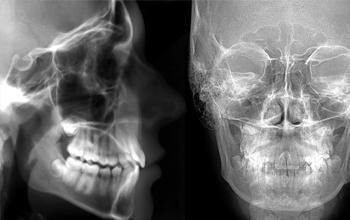

Radiografía cefalográfica lateral

La radiografía cefalográfica lateral capta imágenes, mediante rayos X, de un costado del cráneo y puede detectarte posibles malformaciones y enfermedades.